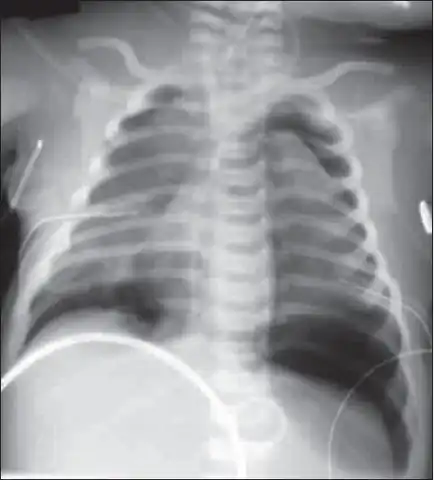

X-ray showing lung damage in response to meconium in a newborn. | |